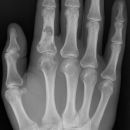

Fraktur MC5